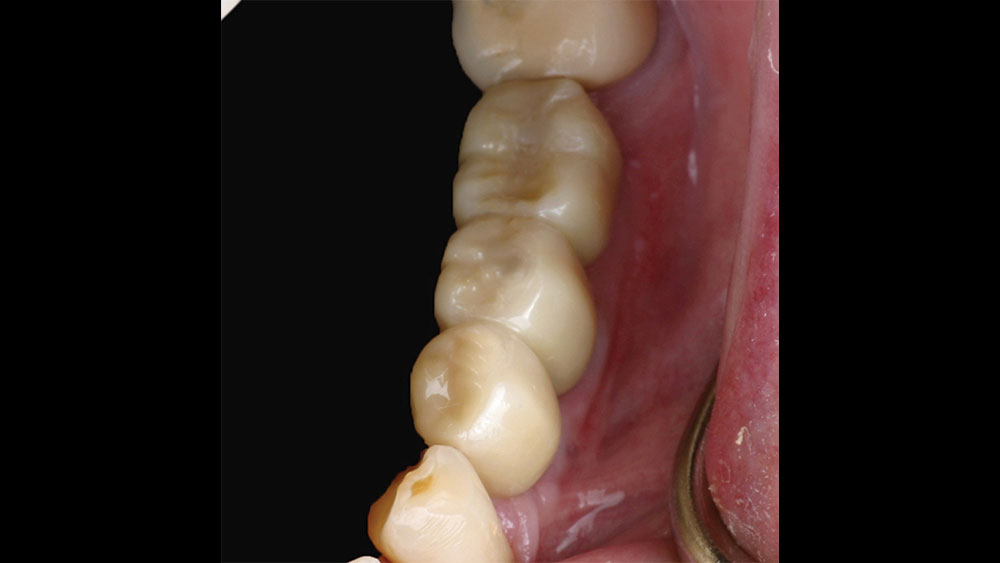

The patient selected implant treatment to replace her teeth. Screw-retained crowns were chosen instead of a cementable restoration, primarily due to the ease of retrievability afforded by screw retention. Because the posterior location of the restorations required resistance to occlusal forces as well as acceptable esthetics, I selected BruxZir® zirconia as the material; its high flexural strength and natural translucency fulfilled both requirements.

The question then became whether to use a splinted restoration in the form of a BruxZir screw-retained bridge, or unsplinted BruxZir screw-retained crowns. An assessment of this patient, as well as the pros and cons of both restoration types as previously outlined, led to the decision that an unsplinted restoration was the preferred treatment in this case. The key factors in this choice were as follows:

CONCLUSION

Cases involving multiple adjacent restorations will always raise the question of whether a splinted or unsplinted approach is the better option. By carefully analyzing the pros and cons of each restoration type and weighing those factors against the particular considerations and priorities involved in that patient’s individual case, the informed clinician can make a decision that’s best for long-term survivability as well as patient health, comfort and happiness.